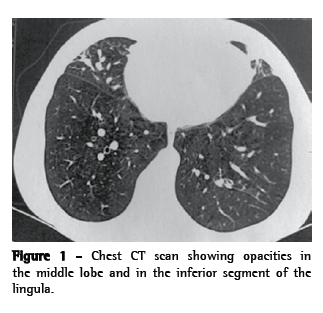

Because the productive cough persisted, the patient underwent chest CT, which revealed opacities in the middle lobe, the inferior segment of the lingula, and the anterior segment of the right upper lobe, as well as thickening of the peribronchial sheaths and signs of mucoid impaction (Figure 1). A second fiberoptic bronchoscopy revealed the persistence of a large quantity of diffuse yellowish mucus, and the microbiological analysis of the material revealed the growth of Staphylococcus aureus (50,000 CFU/mL). The patient underwent treatment with ciprofloxacin (500 mg, bid) for 21 days, after which she remained symptomatic.